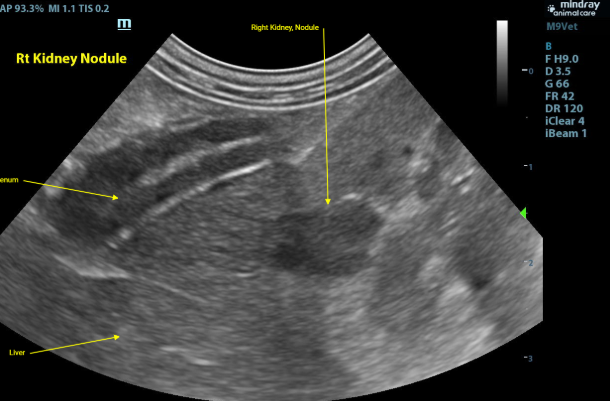

Kidneys - Both kidneys were found to have normal size (Lt/Rt = 3.8 /4.0cm). With a normal overall shape with coarse mild to moderately hyperechoic renal cortices which are mildly enlarged. There was mild loss of the corticomedullary junction distinction. There were a few small thin-walled anechoic cortical cysts seen throughout both kidneys. There is a homogenous, well defined, hypoechoic very mildly capsule deforming nodule affecting the corticomedullary region in the convex portion of the right kidney. (1.1x0.8cm)

Image 1 - Right kidney in sagittal with small hypoechoic well defined nodule